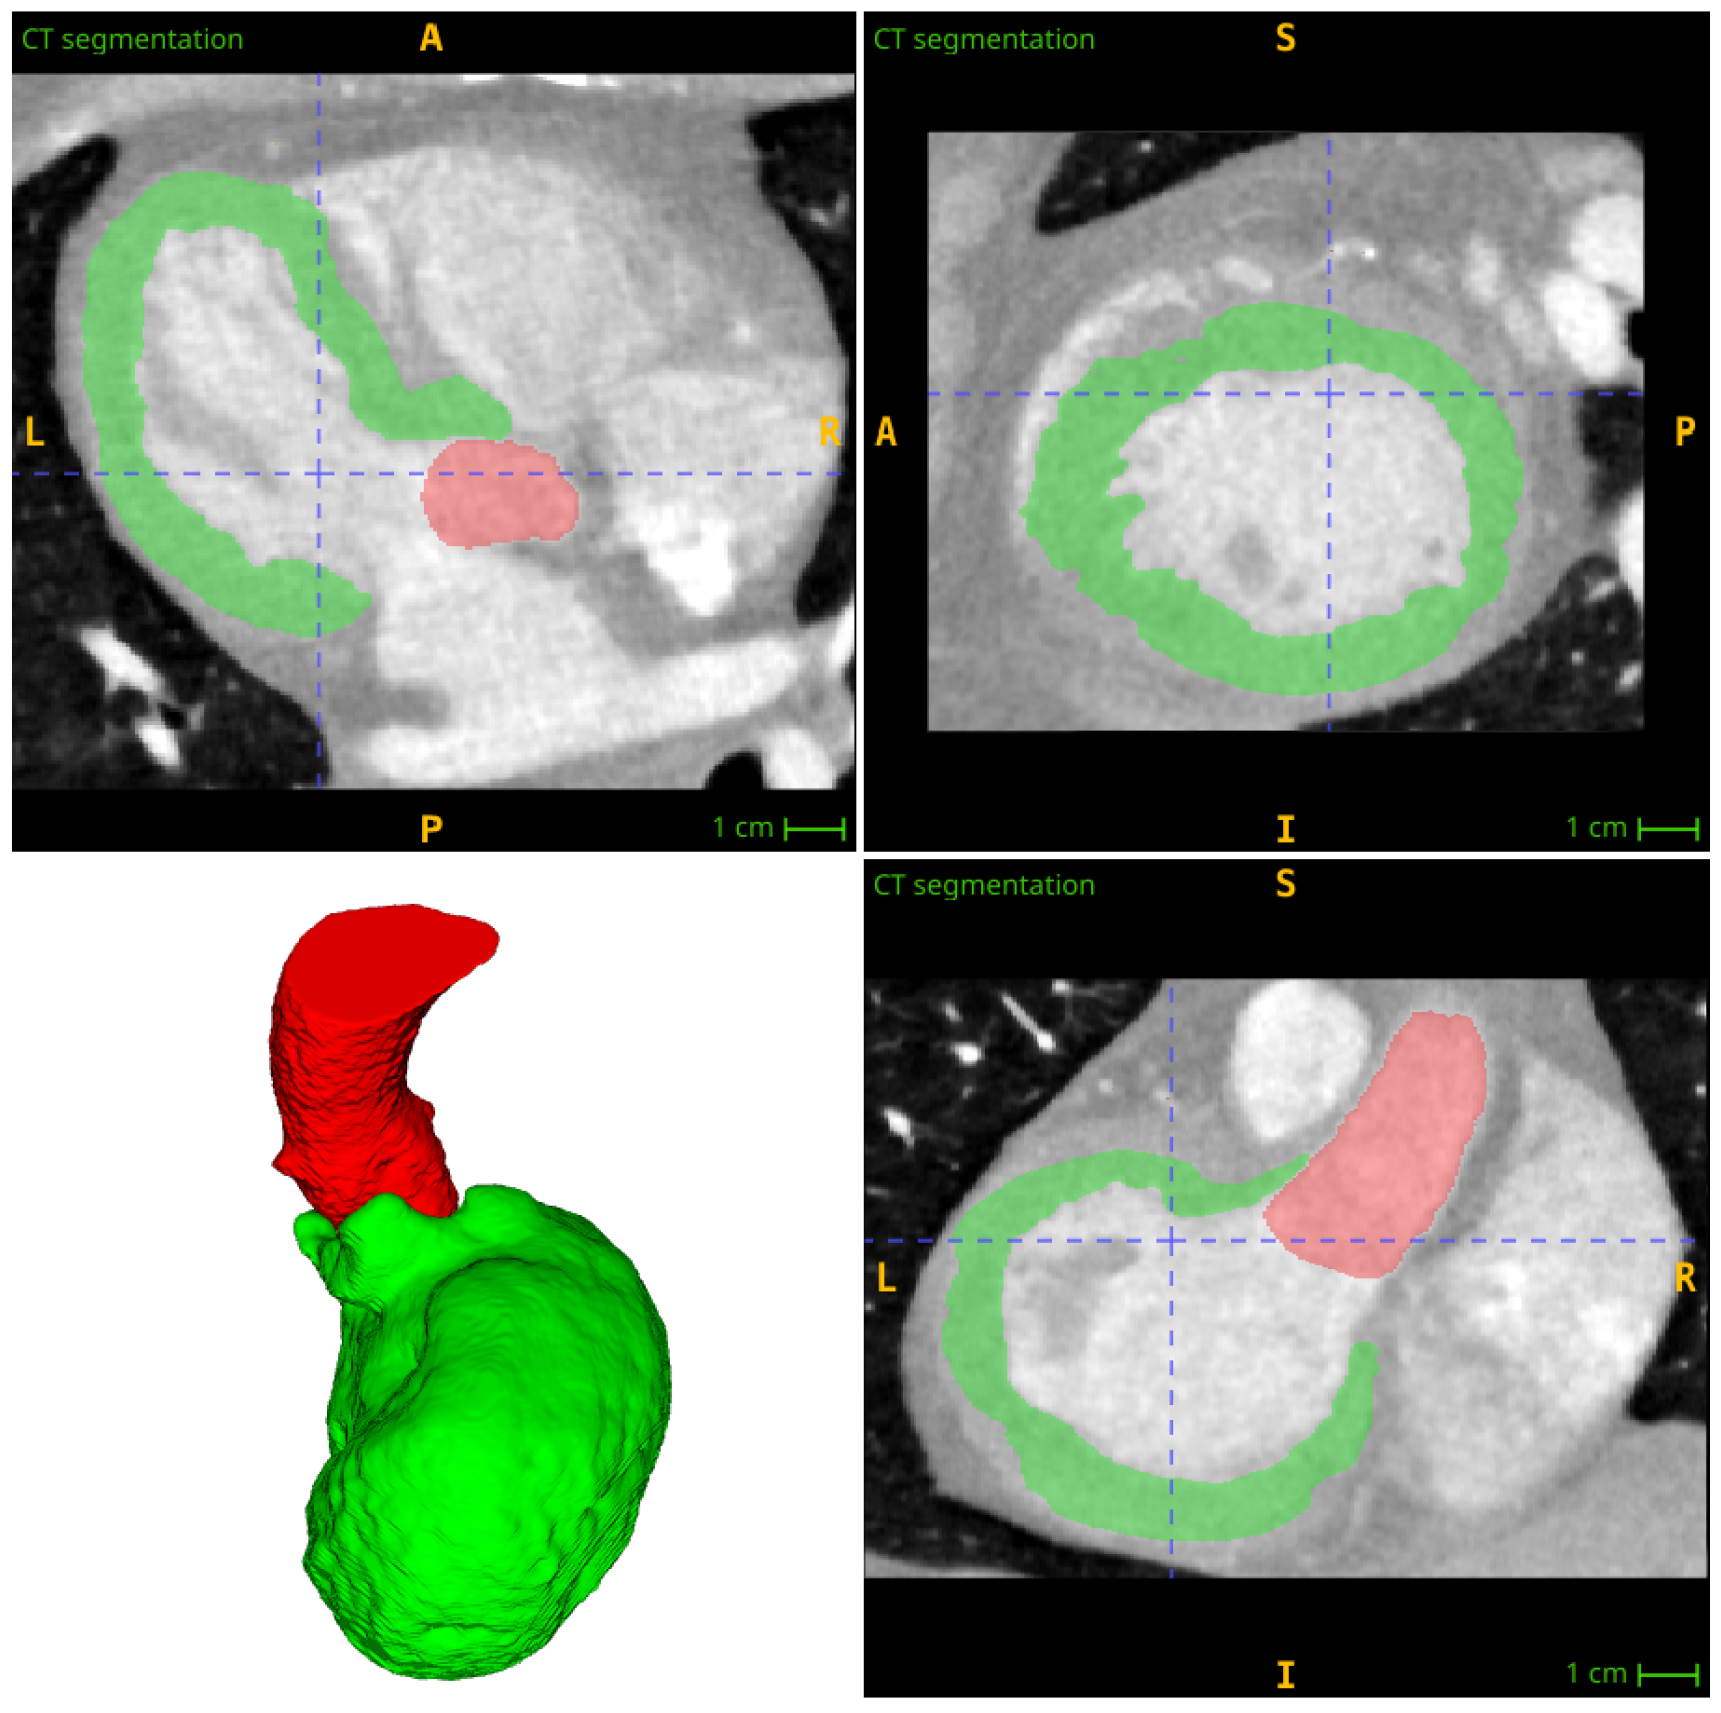

In the third stage of the process, the myocardial wall is segmented using threshold-based techniques. The average intensity of myocardial wall voxels in computed tomography perfusion images is typically found to be in the range [ 80 ; 140 ] HU. The left ventricular wall, exhibiting heightened intensity values due to contrast enhancement, is situated adjacent to the left ventricular cavity. This wall can be distinguished from the atria by a plane that traverses the mitral valve. During segmentation, we prioritize identifying these boundaries, due to the notable change in intensity observed at their boundaries. We set all the extremely low intensities, all the negative intensities, and all the extremely high intensities to zero. The volume of the left ventricular wall is extracted as a contiguous region, encompassing the plane passing through the mitral valve (Figure 2). It is estimated that the position of the mitral valve plane is that plane which is perpendicular to the left ventricular axis and which passes through the interface between the right and left atrium.

Figure 2. Segmentation of the aorta and left ventricle walls for CTP image: aorta in red color, left ventricle walls in green color.

The myocardial wall is divided into individual zones corresponding to the coronary segments by recursively descending through the coronary tree. As this process is carried out, the ventricle is partitioned, with only the part already belonging to the parent branch being taken. This is conducted in the same way at each branching point until the partitioned myocardial wall corresponding to the terminal segments of the coronary tree has been obtained (Figure 3).

Figure 3. Final partitioning of the left ventricle wall with supplying coronary arteries (the same color as a segment) and aorta (shown in red).